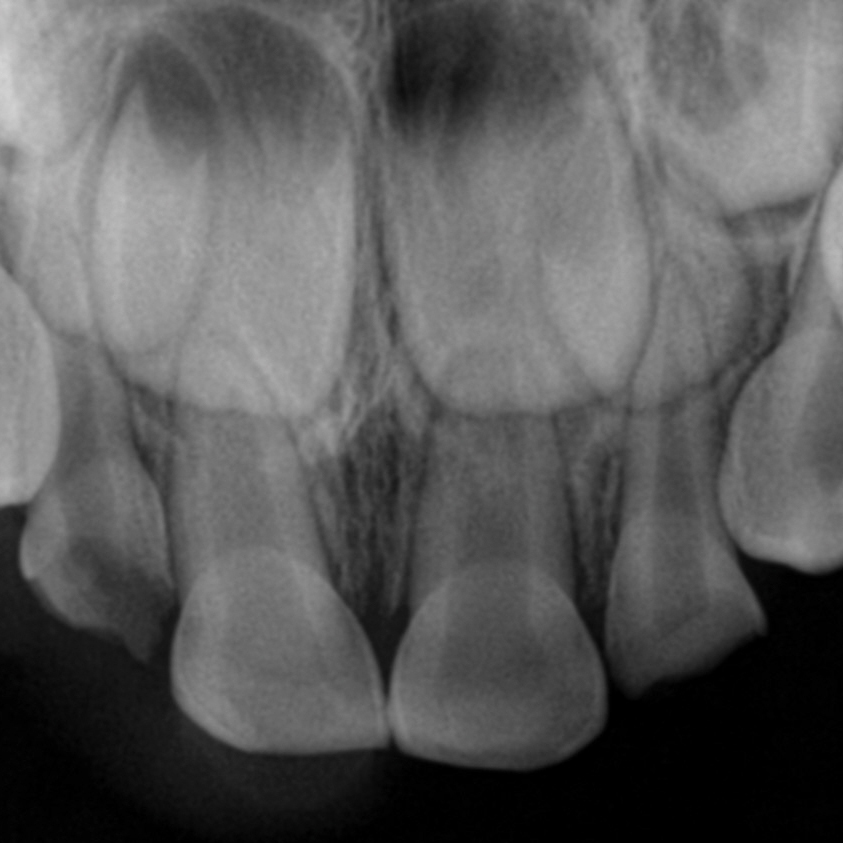

Due to Zirconia’s strength and superior esthetics, Zirconia crowns are often the best and most reliable choice to use in restoring these challenging cases. The first thing to consider when planning treatment to restore an anterior tooth in a patient with cross-bite is whether the case is a dental or skeletal class-three malocclusion. This determination will dictate the course of treatment. Let me explain.

If you are treating a true skeletal class-three case, you will want to prepare the tooth mostly on the facial surface. This will allow the crown to seat far enough lingually for it to clear the lower incisors when the child bites into maximum intercuspation.

If, however, the patient has a mildly trapped dental class-thee occlusion and you feel you might be able to correct the situation by crowning the anterior incisors, you will want to prepare the tooth mostly from the lingual side. This will allow you to flair the crown labially when seating. Often it proves helpful to adjust the incisal edges of the lower incisors, in many cases thus allowing for the anterior upper and lower teeth to meet end to end.